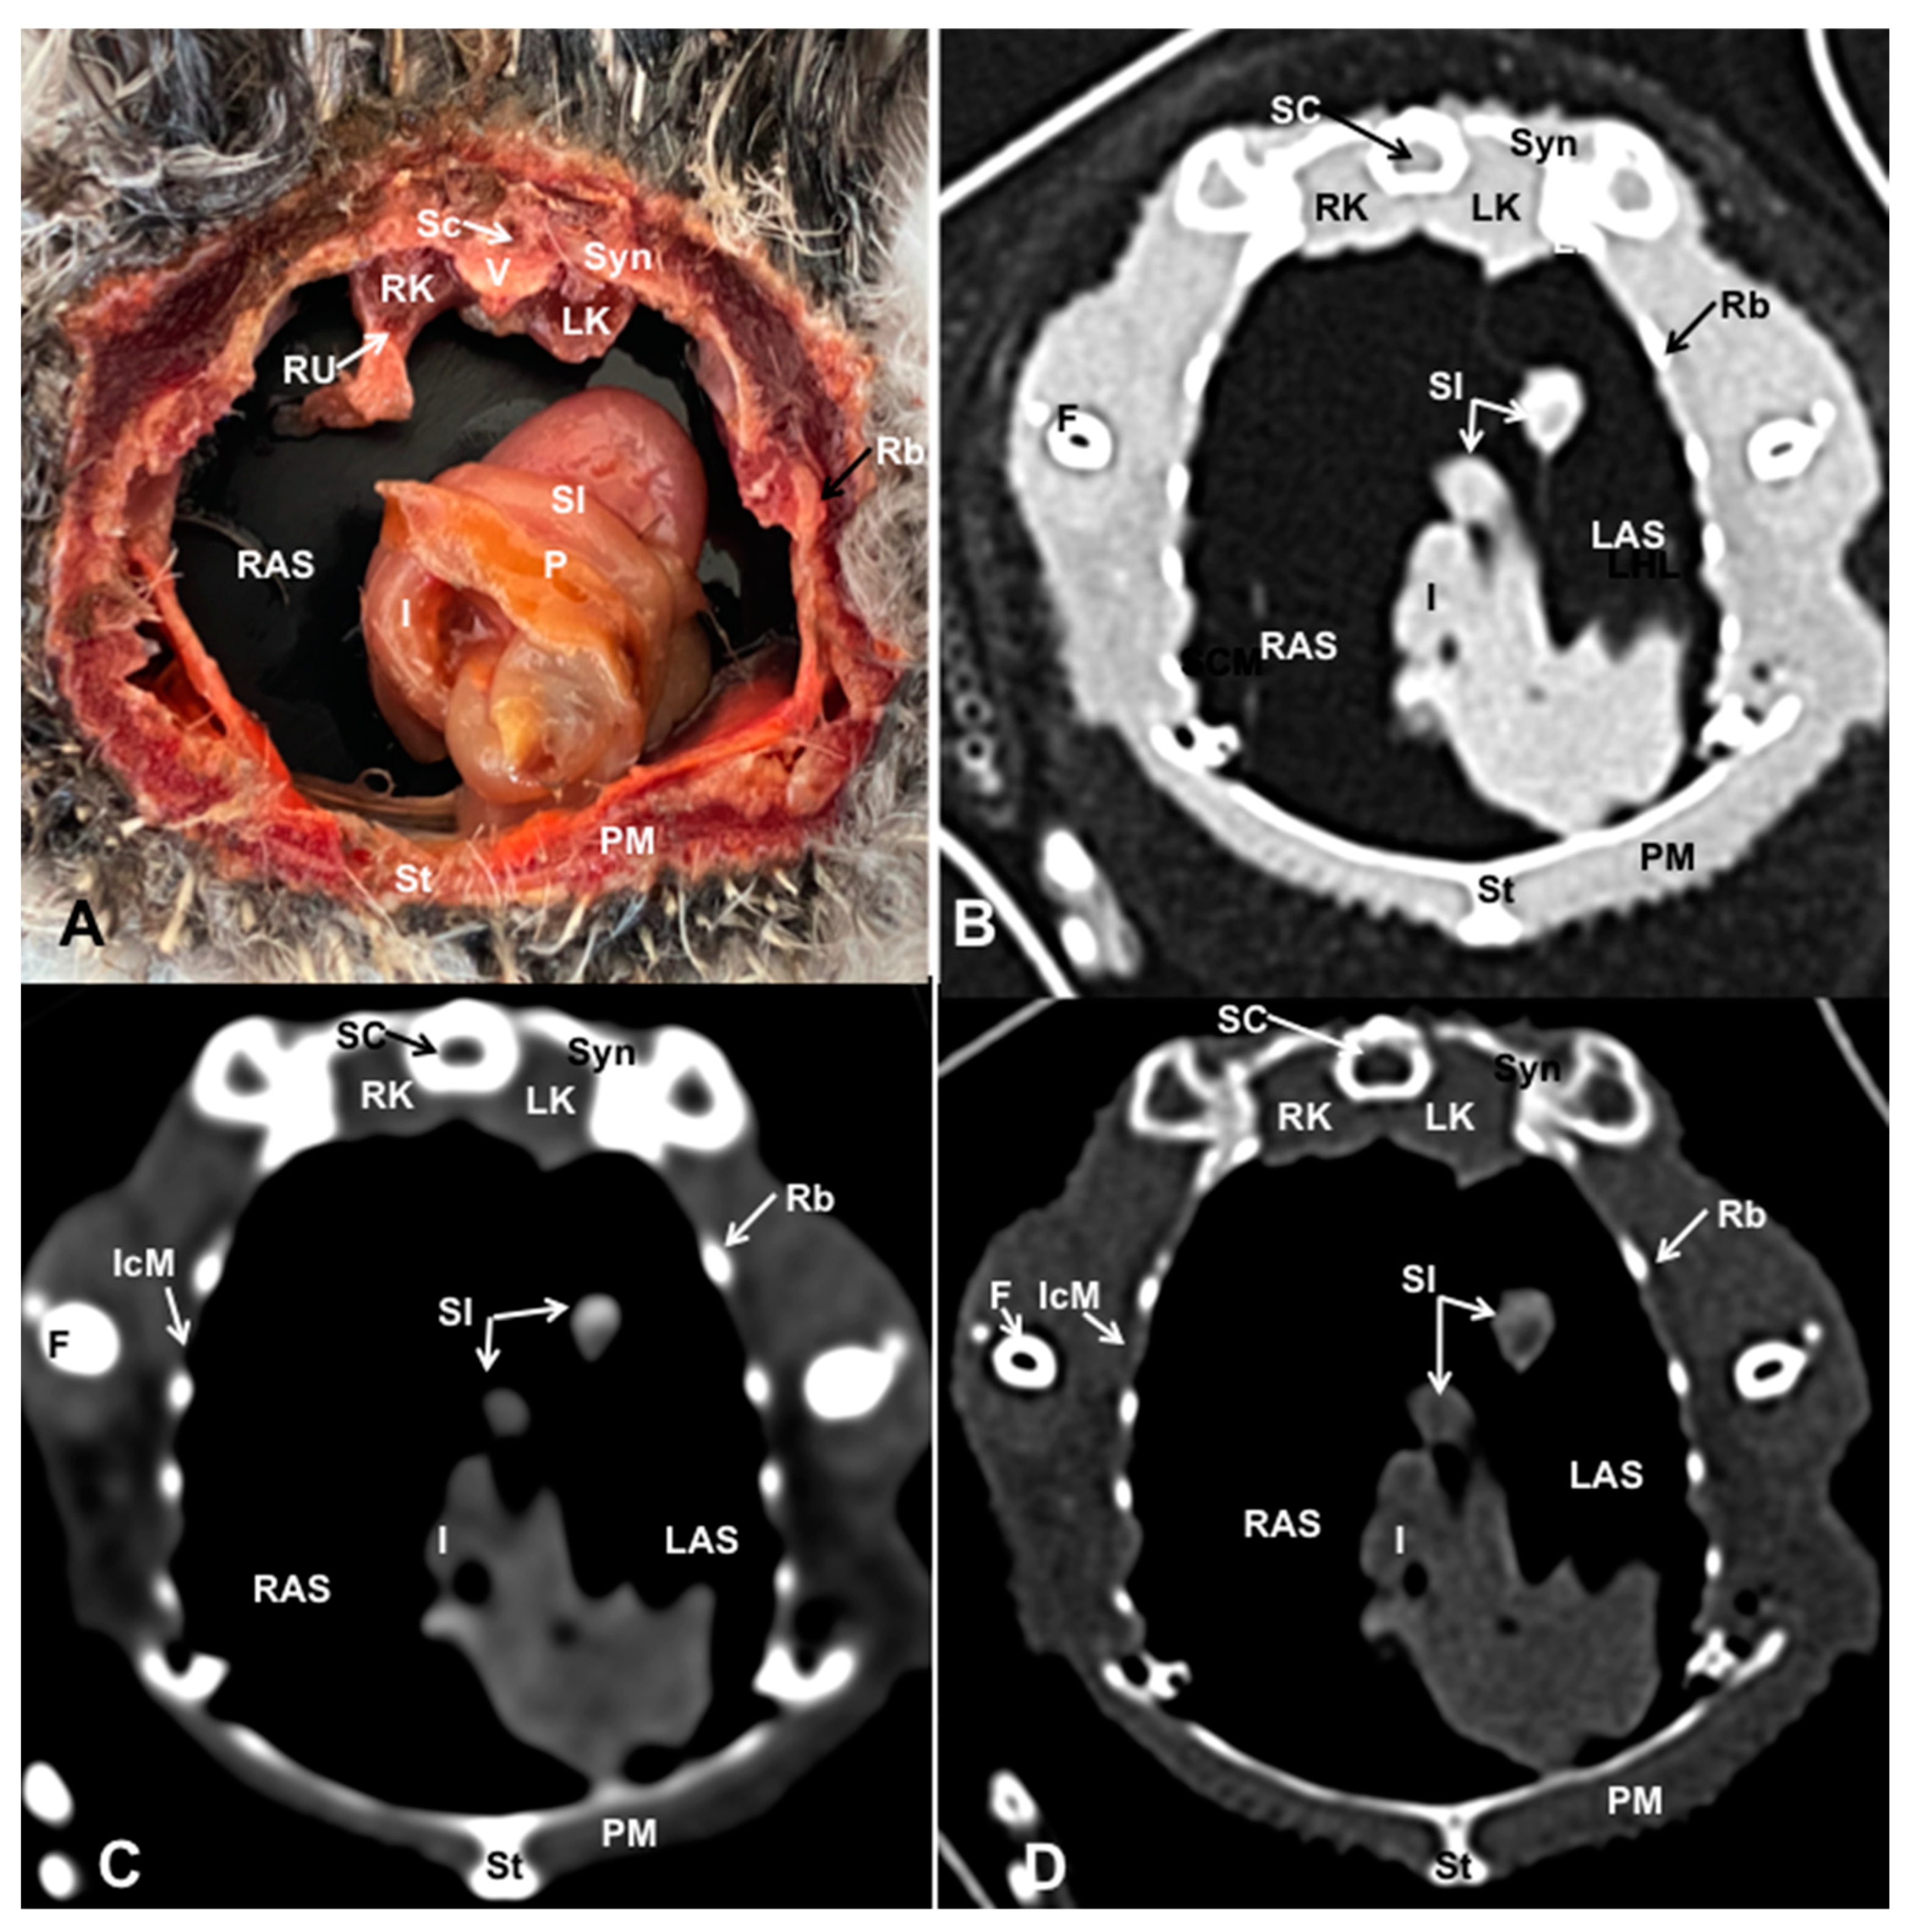

3.1. Anatomical Dissections and Cross-Sections

3.2. Computed Tomography Images